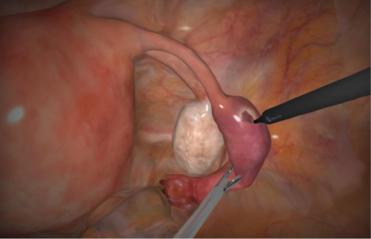

Этапы сальпинготомии: лапароскопия (предпочтительно) или лапаротомия (нижнесрединный продольный разрез или поперечный по Пфаненнштилю), продольное рассечение трубы (рис. 3), удаление плодного яйца, ушивание стенки трубы узловыми швами, туалет брюшной полости, послойное ушивание брюшной полости.

Рис. 3. Сальпинготомия.